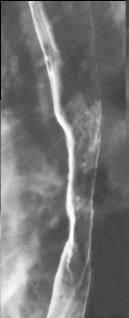

Stade avance un

cancer de oesophage de forme infiltrant . La longeur

de la tumeur depasse 5mm |